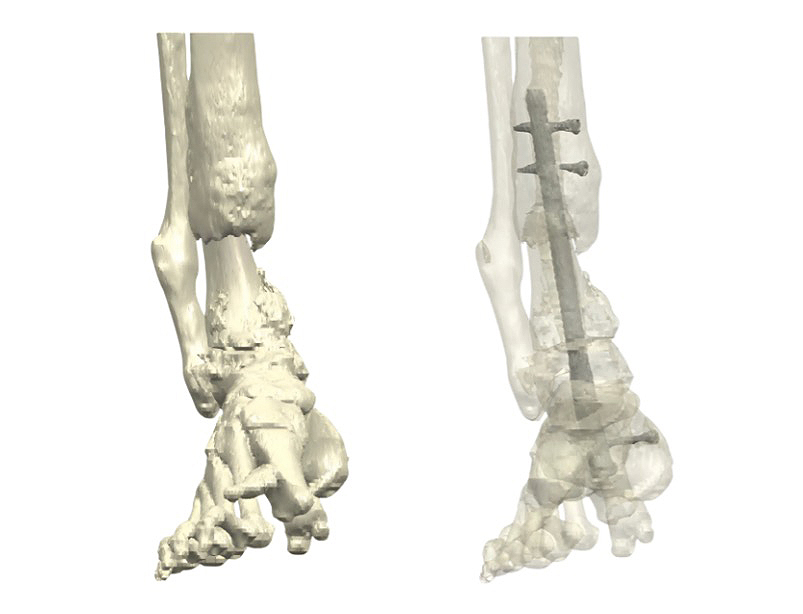

Figure 1: (Left) Preoperative 3D reconstruction of the distal tibia, demonstrating the extensive bone loss that occurred following allograft failure. (Right) Preoperative imaging shows failed fixation, a broken nail, and non-union of the distal tibia.

Massive bone defects of the distal tibia are rare, yet they represent some of the most challenging reconstructive scenarios in

orthopedic surgery. They typically occur after trauma, infection, tumor resection, or—as in this case—after the failure of an allograft.